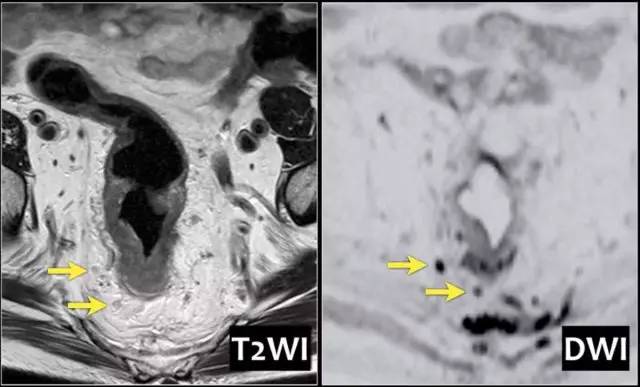

图 25 DWI 有助于检测淋巴结